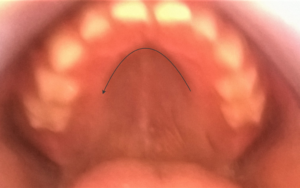

Шишка на небе во рту фото